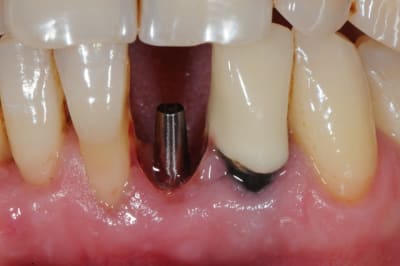

je me permet de ressusciter ce poste car j'ai placé la prothèse il y a un mois.

photo 1: début du cas

photo 2: fin d'intervention

photo 3: j+3mois

photo 4 +5: prise d'empreintes

photo 6-7-8-9: couronne finie.

merci de votre attention :)

PS: le patient ne veux pas faire celle d'à coté.

grr, moi ça me démange...